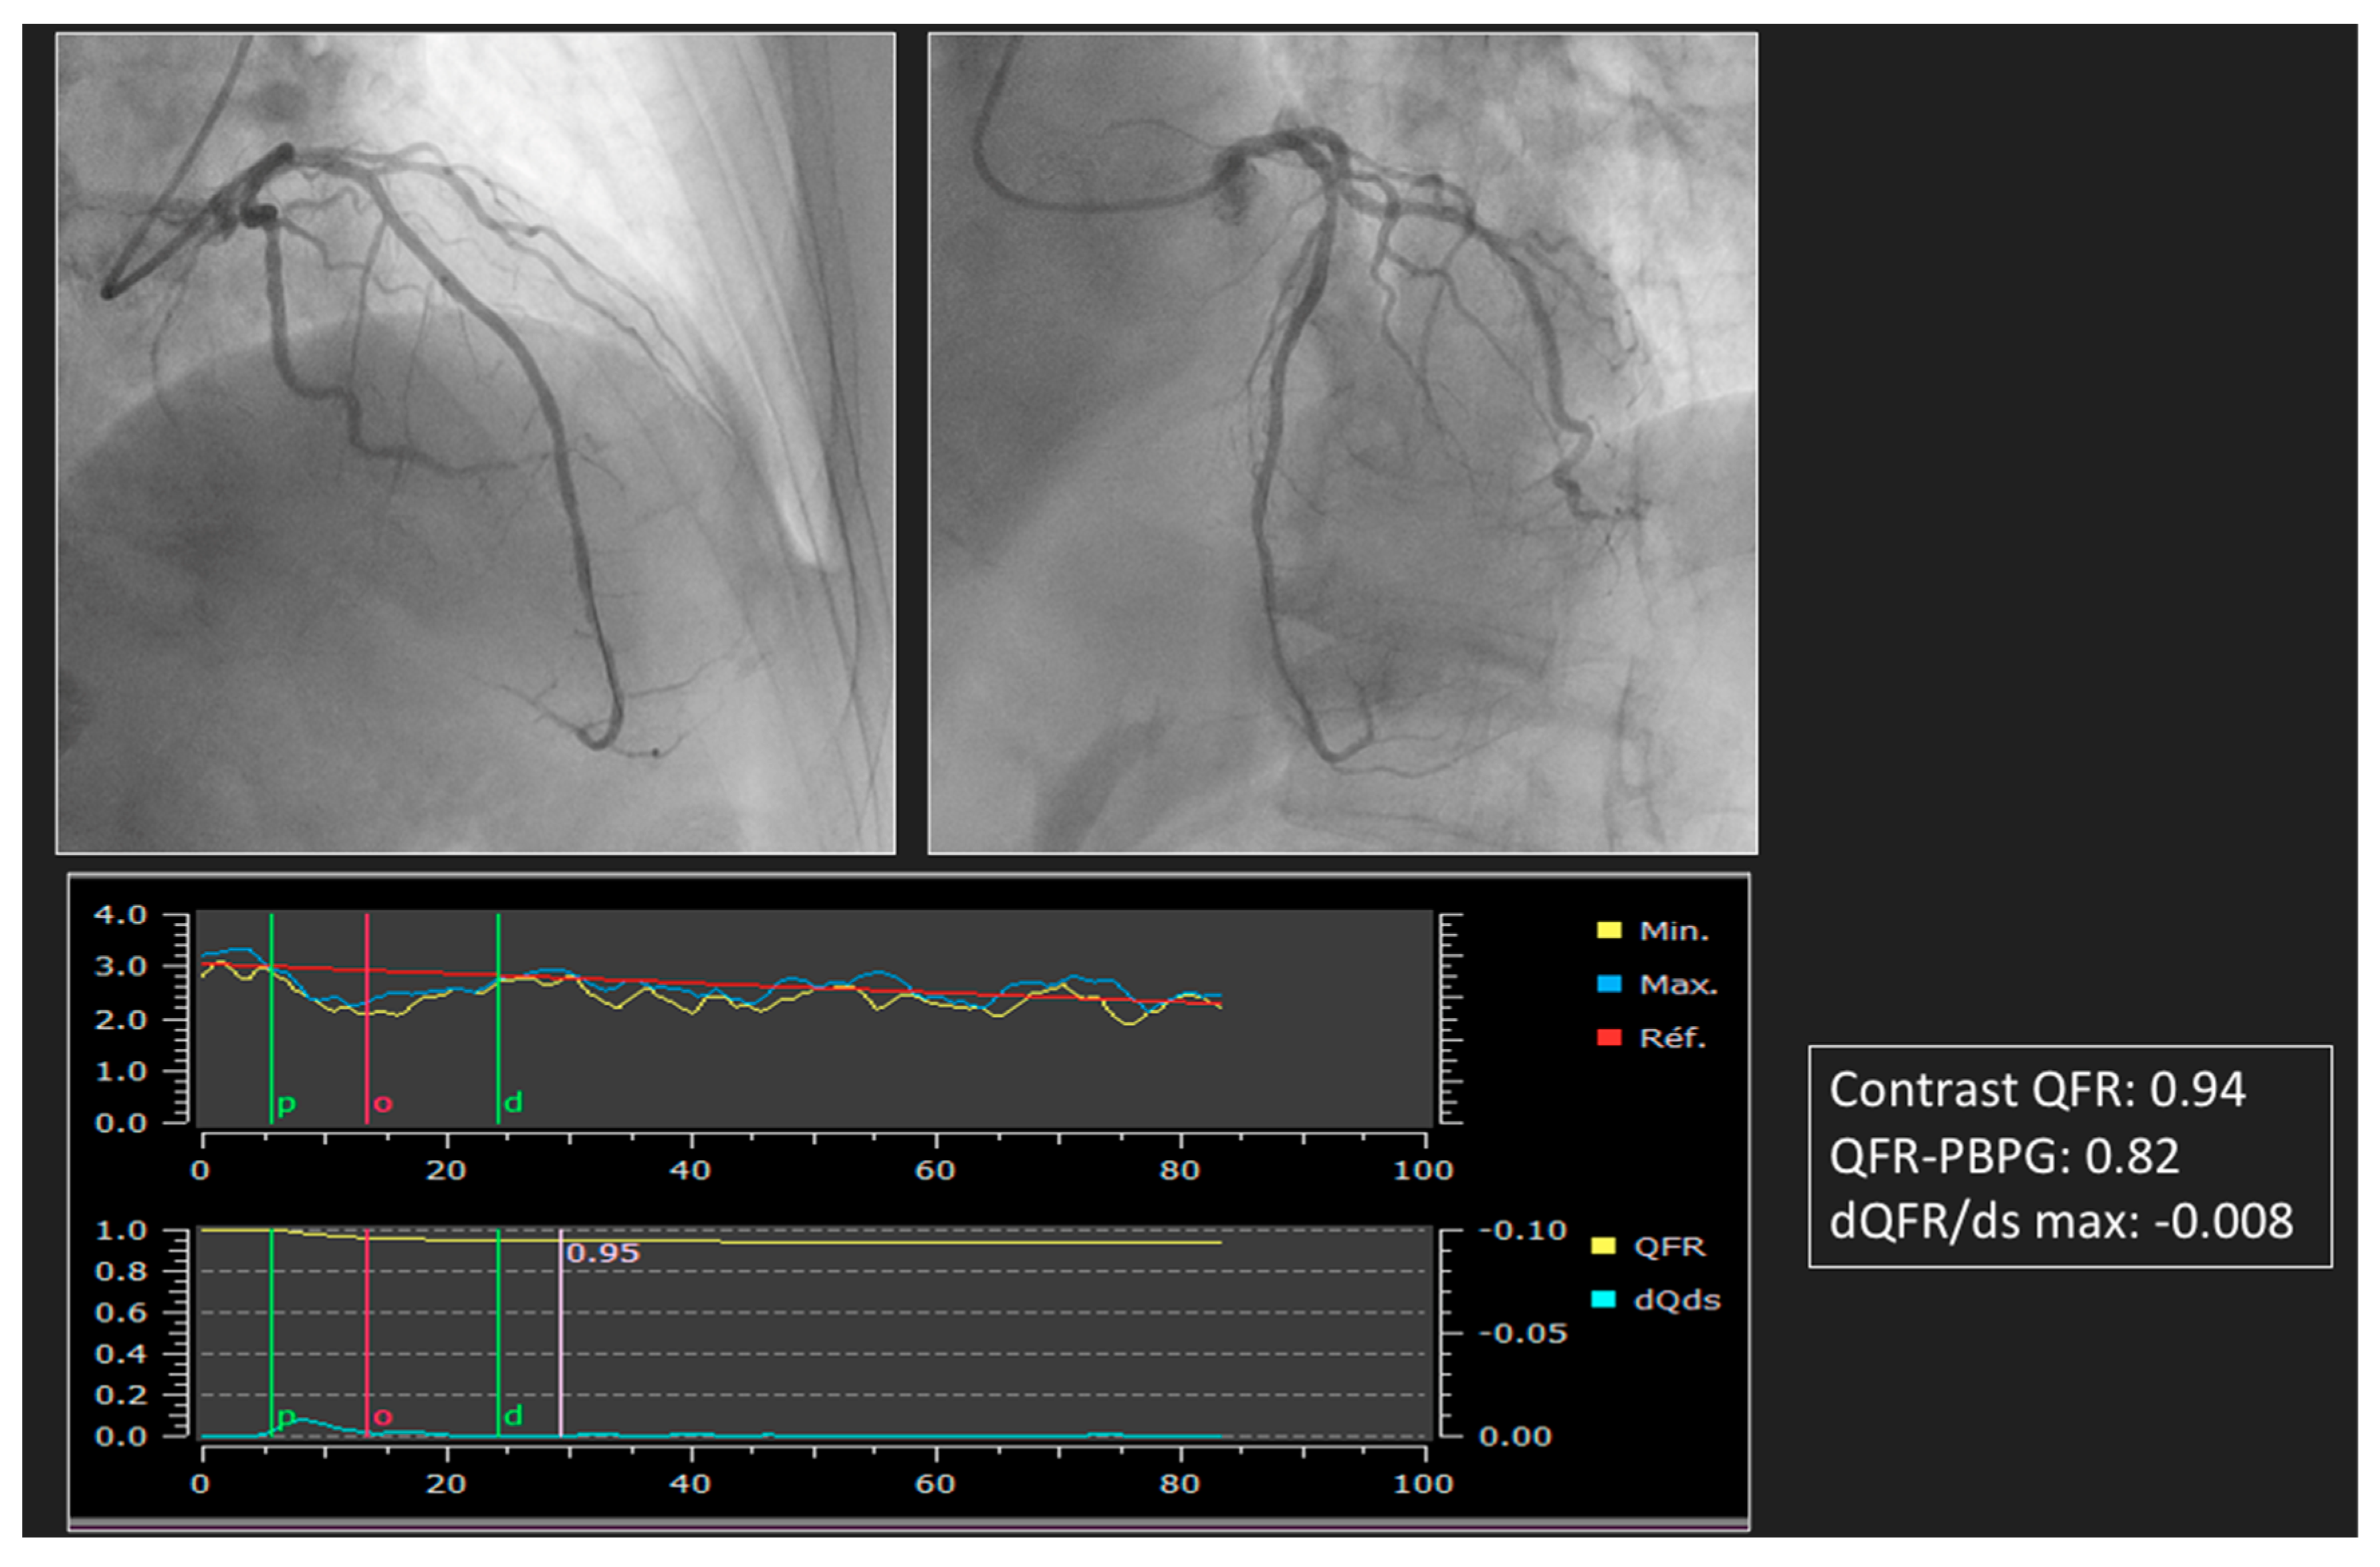

4. Advances in ICA to Assess PCI Results

5. Virtual PCI